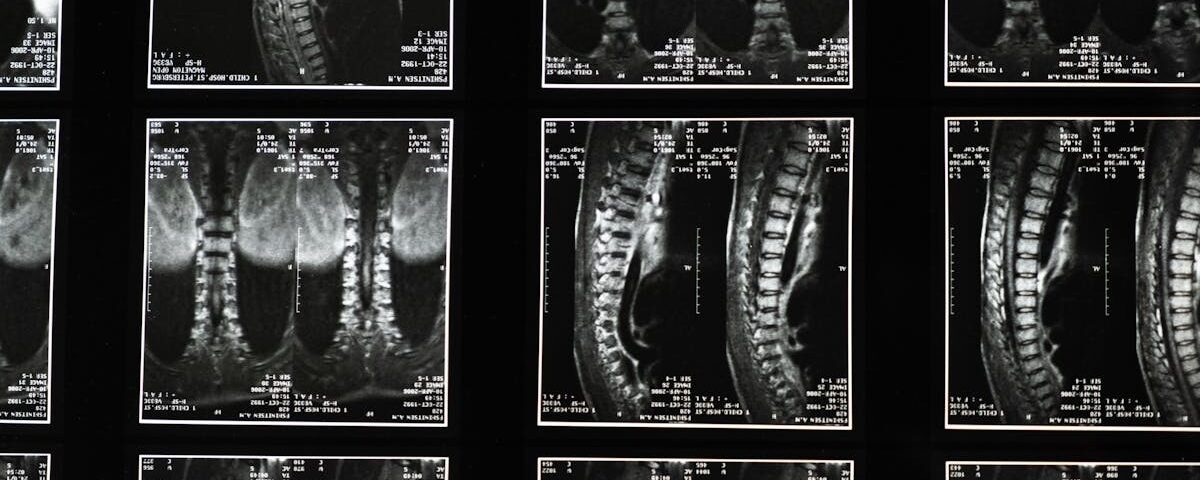

Quels examens sont nécessaires avant de commencer un traitement de décompression pour la sciatique?

Une IRM ou une radiographie est généralement recommandée pour évaluer l’état de la colonne vertébrale.

Quels examens permettent de diagnostiquer la sciatique?

Une IRM ou une radiographie est généralement nécessaire pour confirmer la cause de la sciatique.